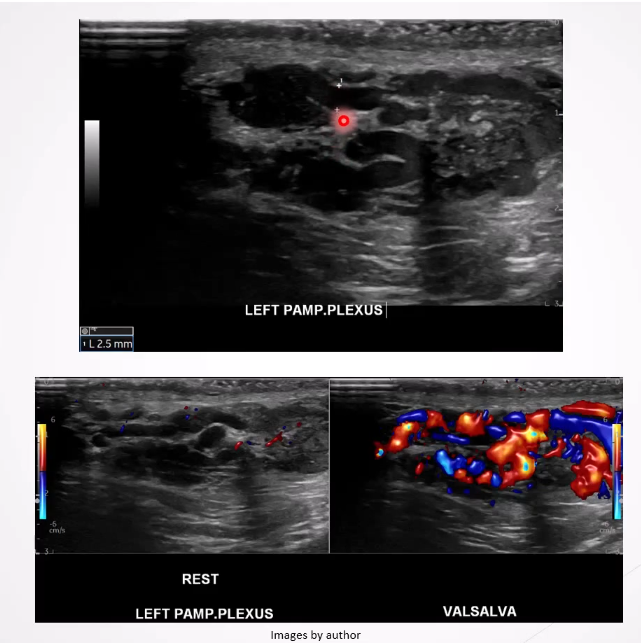

Varicocele: Dilatation of the pampiniform plexus of veins within the spermatic cord and the most common mass of the spermatic cord. Most common cause of male infertility

Ultrasound Appearance:

Dilated veins >2-3 mm in diameter

Scrotal mass with a "Bag of worms" appearance above or posterior to the testes

Veins increase in size with Valsalva maneuver.